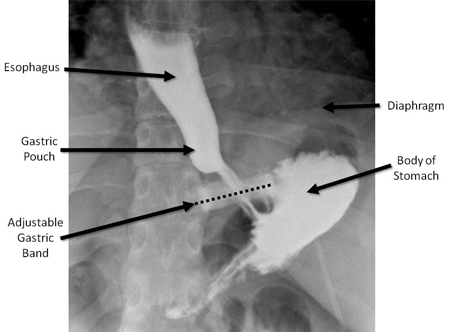

Upper GI series in patient with adjustable gastric band in normal position. The dashed line is superimposed over the band to emphasise the normal angulation of the band, with the left side angled upwards approximately 20-40 degrees from the horizontal. Note the very small pouch between the band and the diaphragm

From collection of Daniel M. Herron, MD